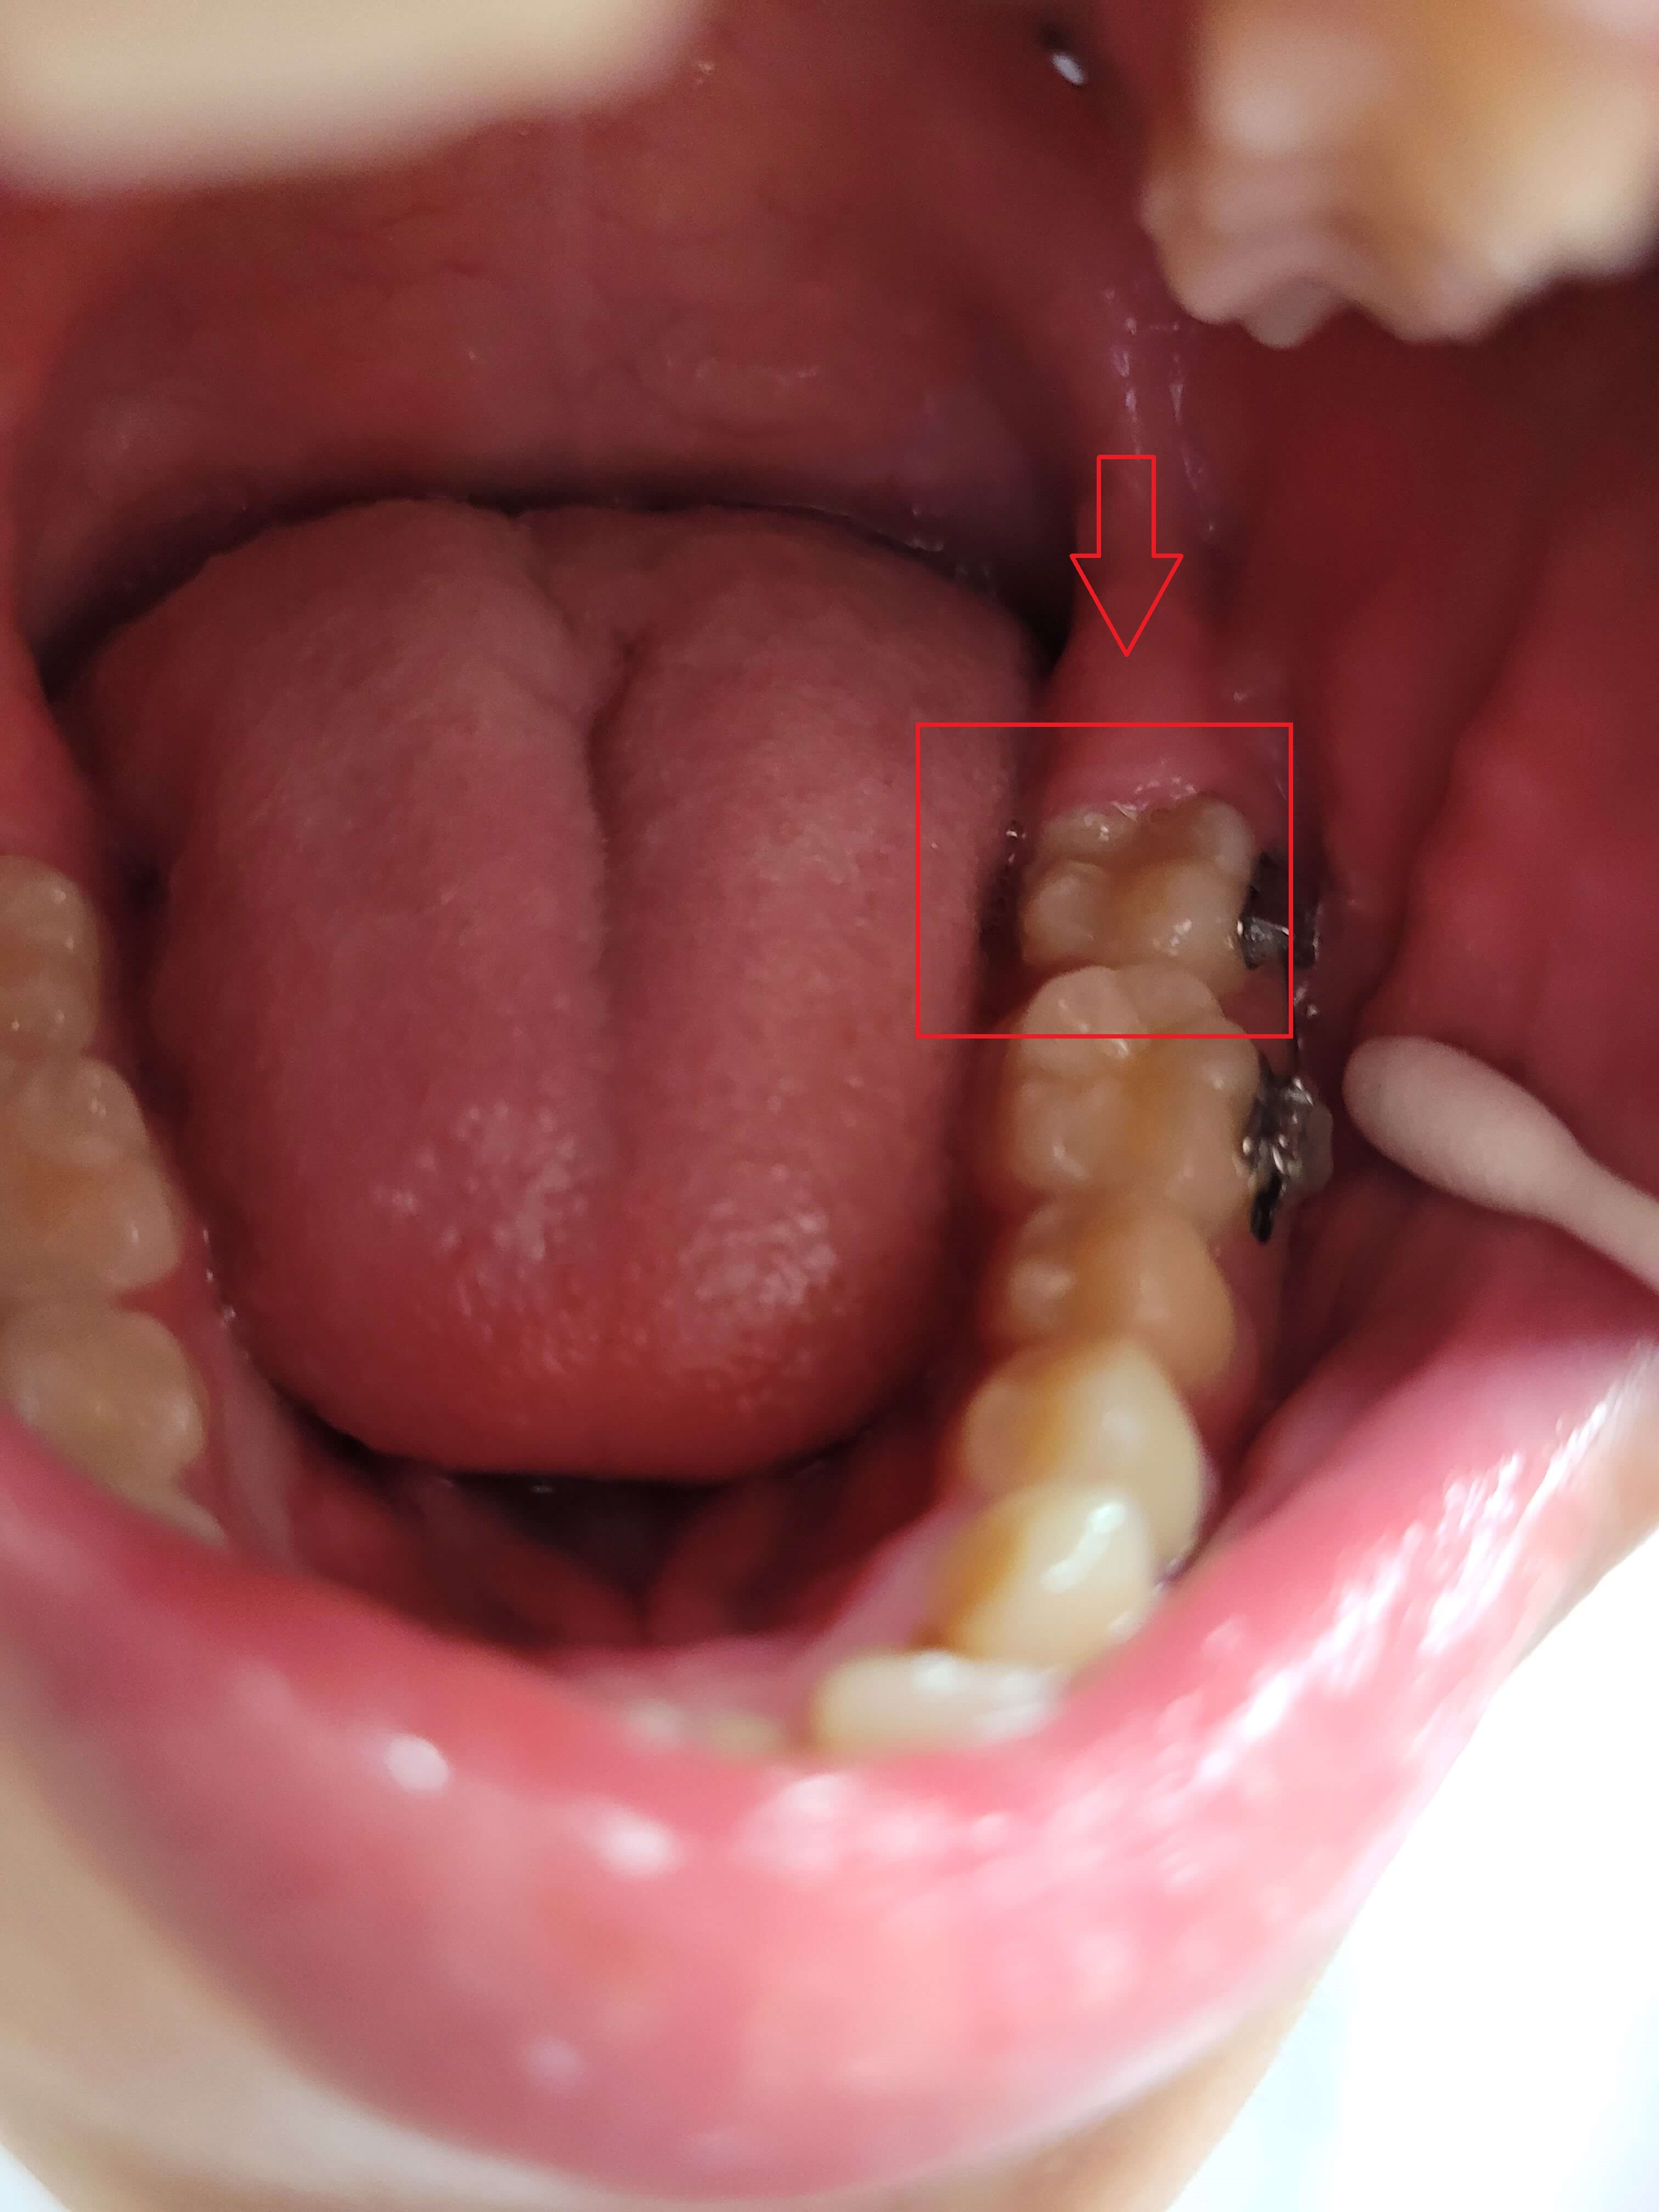

3. 가위교합 + 과개교합 교정실시 (전체브라켓 부착)

3개월간 가위교합 교정이 들어갔고 어느 정도 어금니가 제자리로 돌아왔습니다. 과개교합 교정을 위해 전체브라켓을 부착 하고 있는 사진입니다.

사진에 보면 철사가 S자 모양으로 휘어져 있습니다. 이 철사가 일자형으로 복원이 되면서 틀어진 치아배열을 정돈한다고 하는데 정확한 전문지식은 아니니 참고만 해주세요.

▼ 어금니 교정 후 전체 브라켓 부착